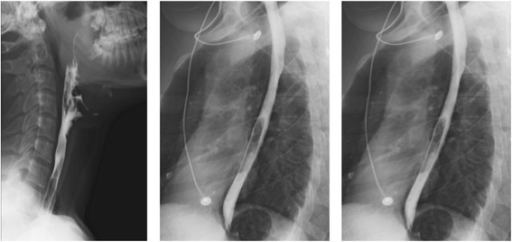

Seringkali pemeriksaan ini menggunakan bantuan cairan kontras untuk visualisasi radioopak yang lebih jelas. Selain mengamati bentuk organ tubuh, fluoroskopi dengan cairan kontras dapat memperlihatkan gerakan organ maupun instrumen medis di dalam rongga tubuh tertentu.[1,3]

Indikasi fluoroskopi adalah sebagai prosedur diagnostik dan sebagai prosedur intervensi. Indikasi diagnostik contohnya untuk menegakkan diagnosa berdasarkan keluhan saluran cerna menggunakan barium enema dan barium swallow, sedangkan contoh teknik intervensi fluoroskopi adalah pada pemasangan stent kateterisasi jantung.[3,4]